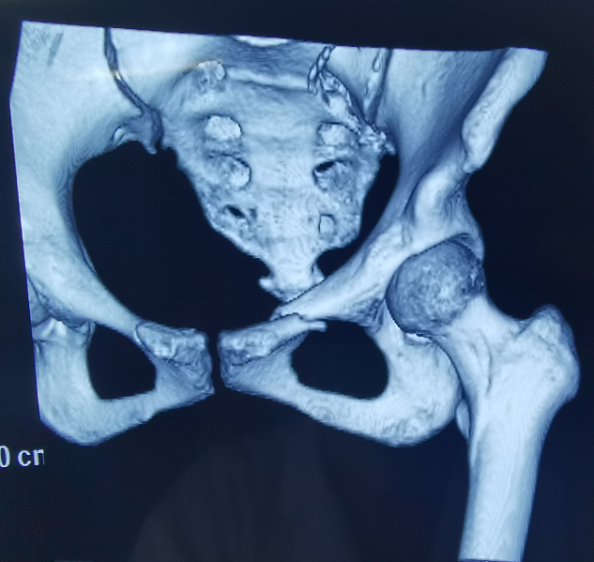

患者為22歲年輕女性,因車禍致骨盆骨折。骨盆骨折是一種復雜的創傷,傳統手術方式需要比較大的切口,而且骨盆內有大量復雜血管和神經,手術難度和風險極大,是很多骨科醫生的禁區。

我國自主研發的天璣?骨科手術機器人,是針對骨骼硬組織的先進技術,已經獲得國際認可,能夠開展脊柱全節段 (頸椎、胸椎、腰椎、骶椎) 疾病、骨盆和四肢等骨折、骨腫瘤以及關節導航等手術。相比傳統手術,機器人輔助手術具有手術創傷小、出血少、并發癥少、康復快的優勢。同時,由于不需通過反復透視來確定置釘位置,從而能減少術中輻射,大大降低患者輻射危害,且手術過程中,由機器人與主刀醫師共同完成手術,大大增加了手術安全性。